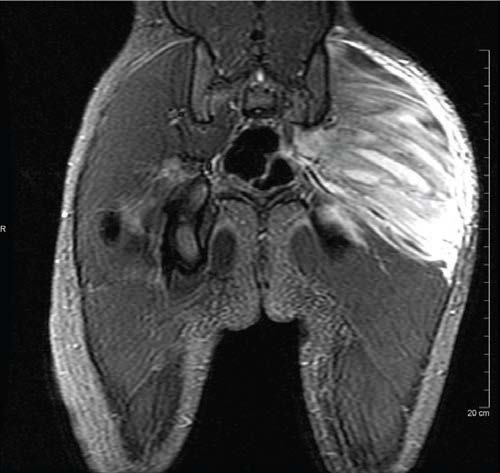

Nishit Patel, MD; Amir Raza, PA-C; Thomas R. Lewis, MD; Sandeep G. Prabhu, MD; Faridali G. Ramji, MD

A 19-month-old girl was brought into the orthopedic clinic by her parents for a chief concern of limping on her right leg for 9 days.